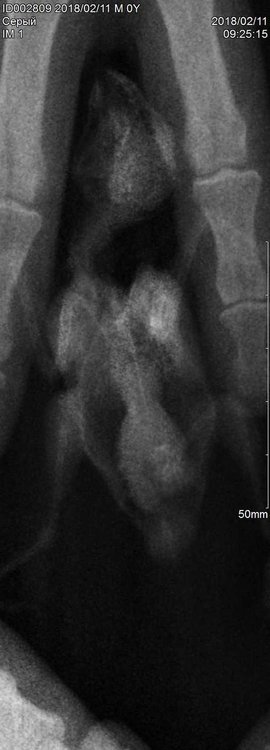

8.1.1. каковы их результаты -  Последний раз сдавали помет на копрограмму  04.02.2018, паразитов не обнаружили, рентген сделали сегодня, 11.02.2018

Рентген птички сделали сегодня, хирург сказал, что в птицах не разбирается, но какое-то затемнение внизу птички есть. Качество не очень, так как птичка очень маленькая и сложно было его сделать. Все снимки прилагаю. Зося, посмотрите, пожалуйста, что с моей птичкой? Чем ей помочь, как лечить? Ей очень плохо! Снегирик боится рук, стрессует, а сейчас вообще в панике. Сидит, дрожит, хвостик поджимает вниз, видимо у него что-то болит.